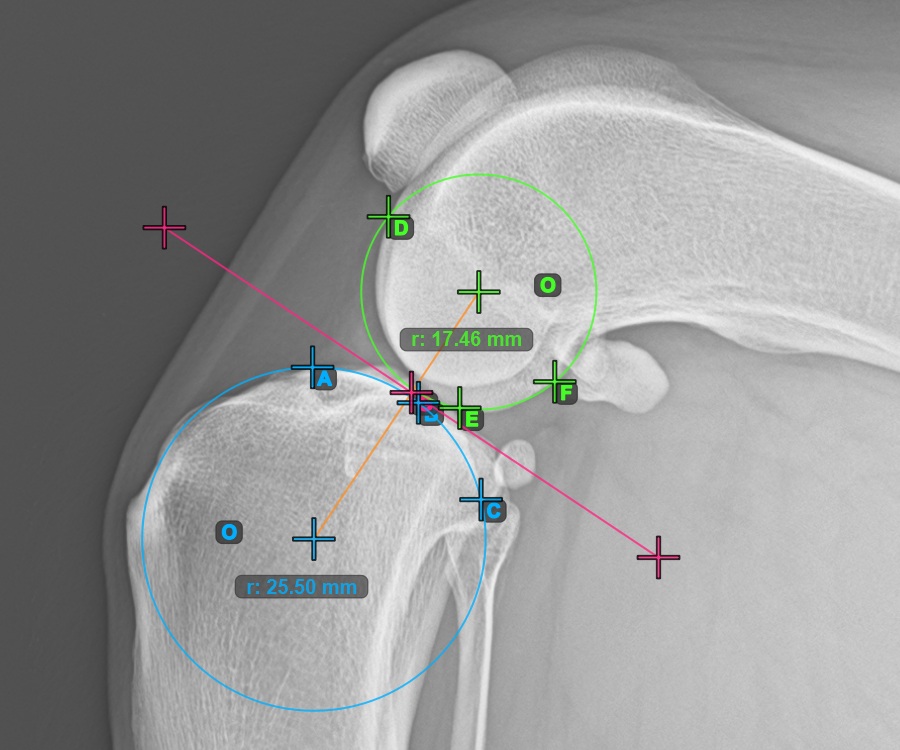

Start the measurement by marking the three points on the Condylus Medialis Tibialis.

Mark the three points on the main condylus of the tibial bone (Medialis Tibialis). Regardless of the order, make sure to mark the most cranial point, the most caudal point and the midpoint of the Medialis Tibialis. A circle will be automatically constructed based on the three placed points.

The image below represents a typical placement of the three points on the Condylus Medialis Tibialis.